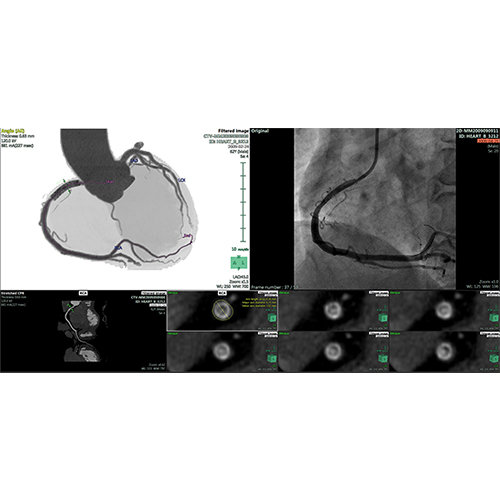

ANYTHINK 经导管主动脉瓣膜置换术分析系统